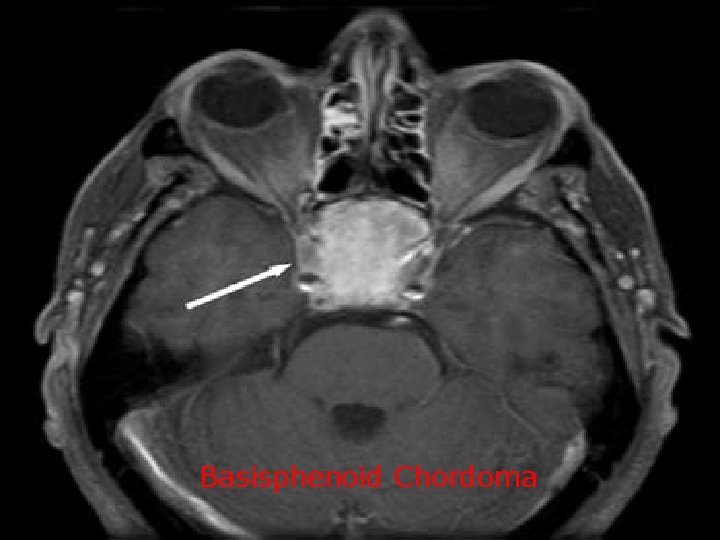

Basisphenoid Chordoma